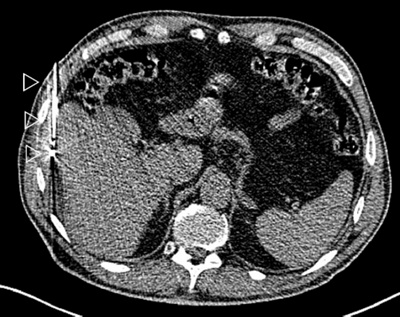

leber1

Thermoablation einer Lebermetastase (weisser Pfeil) durch CT-gesteuerte Platzierung einer Mikrowellensonde (Pfeilköpfe).

leber2